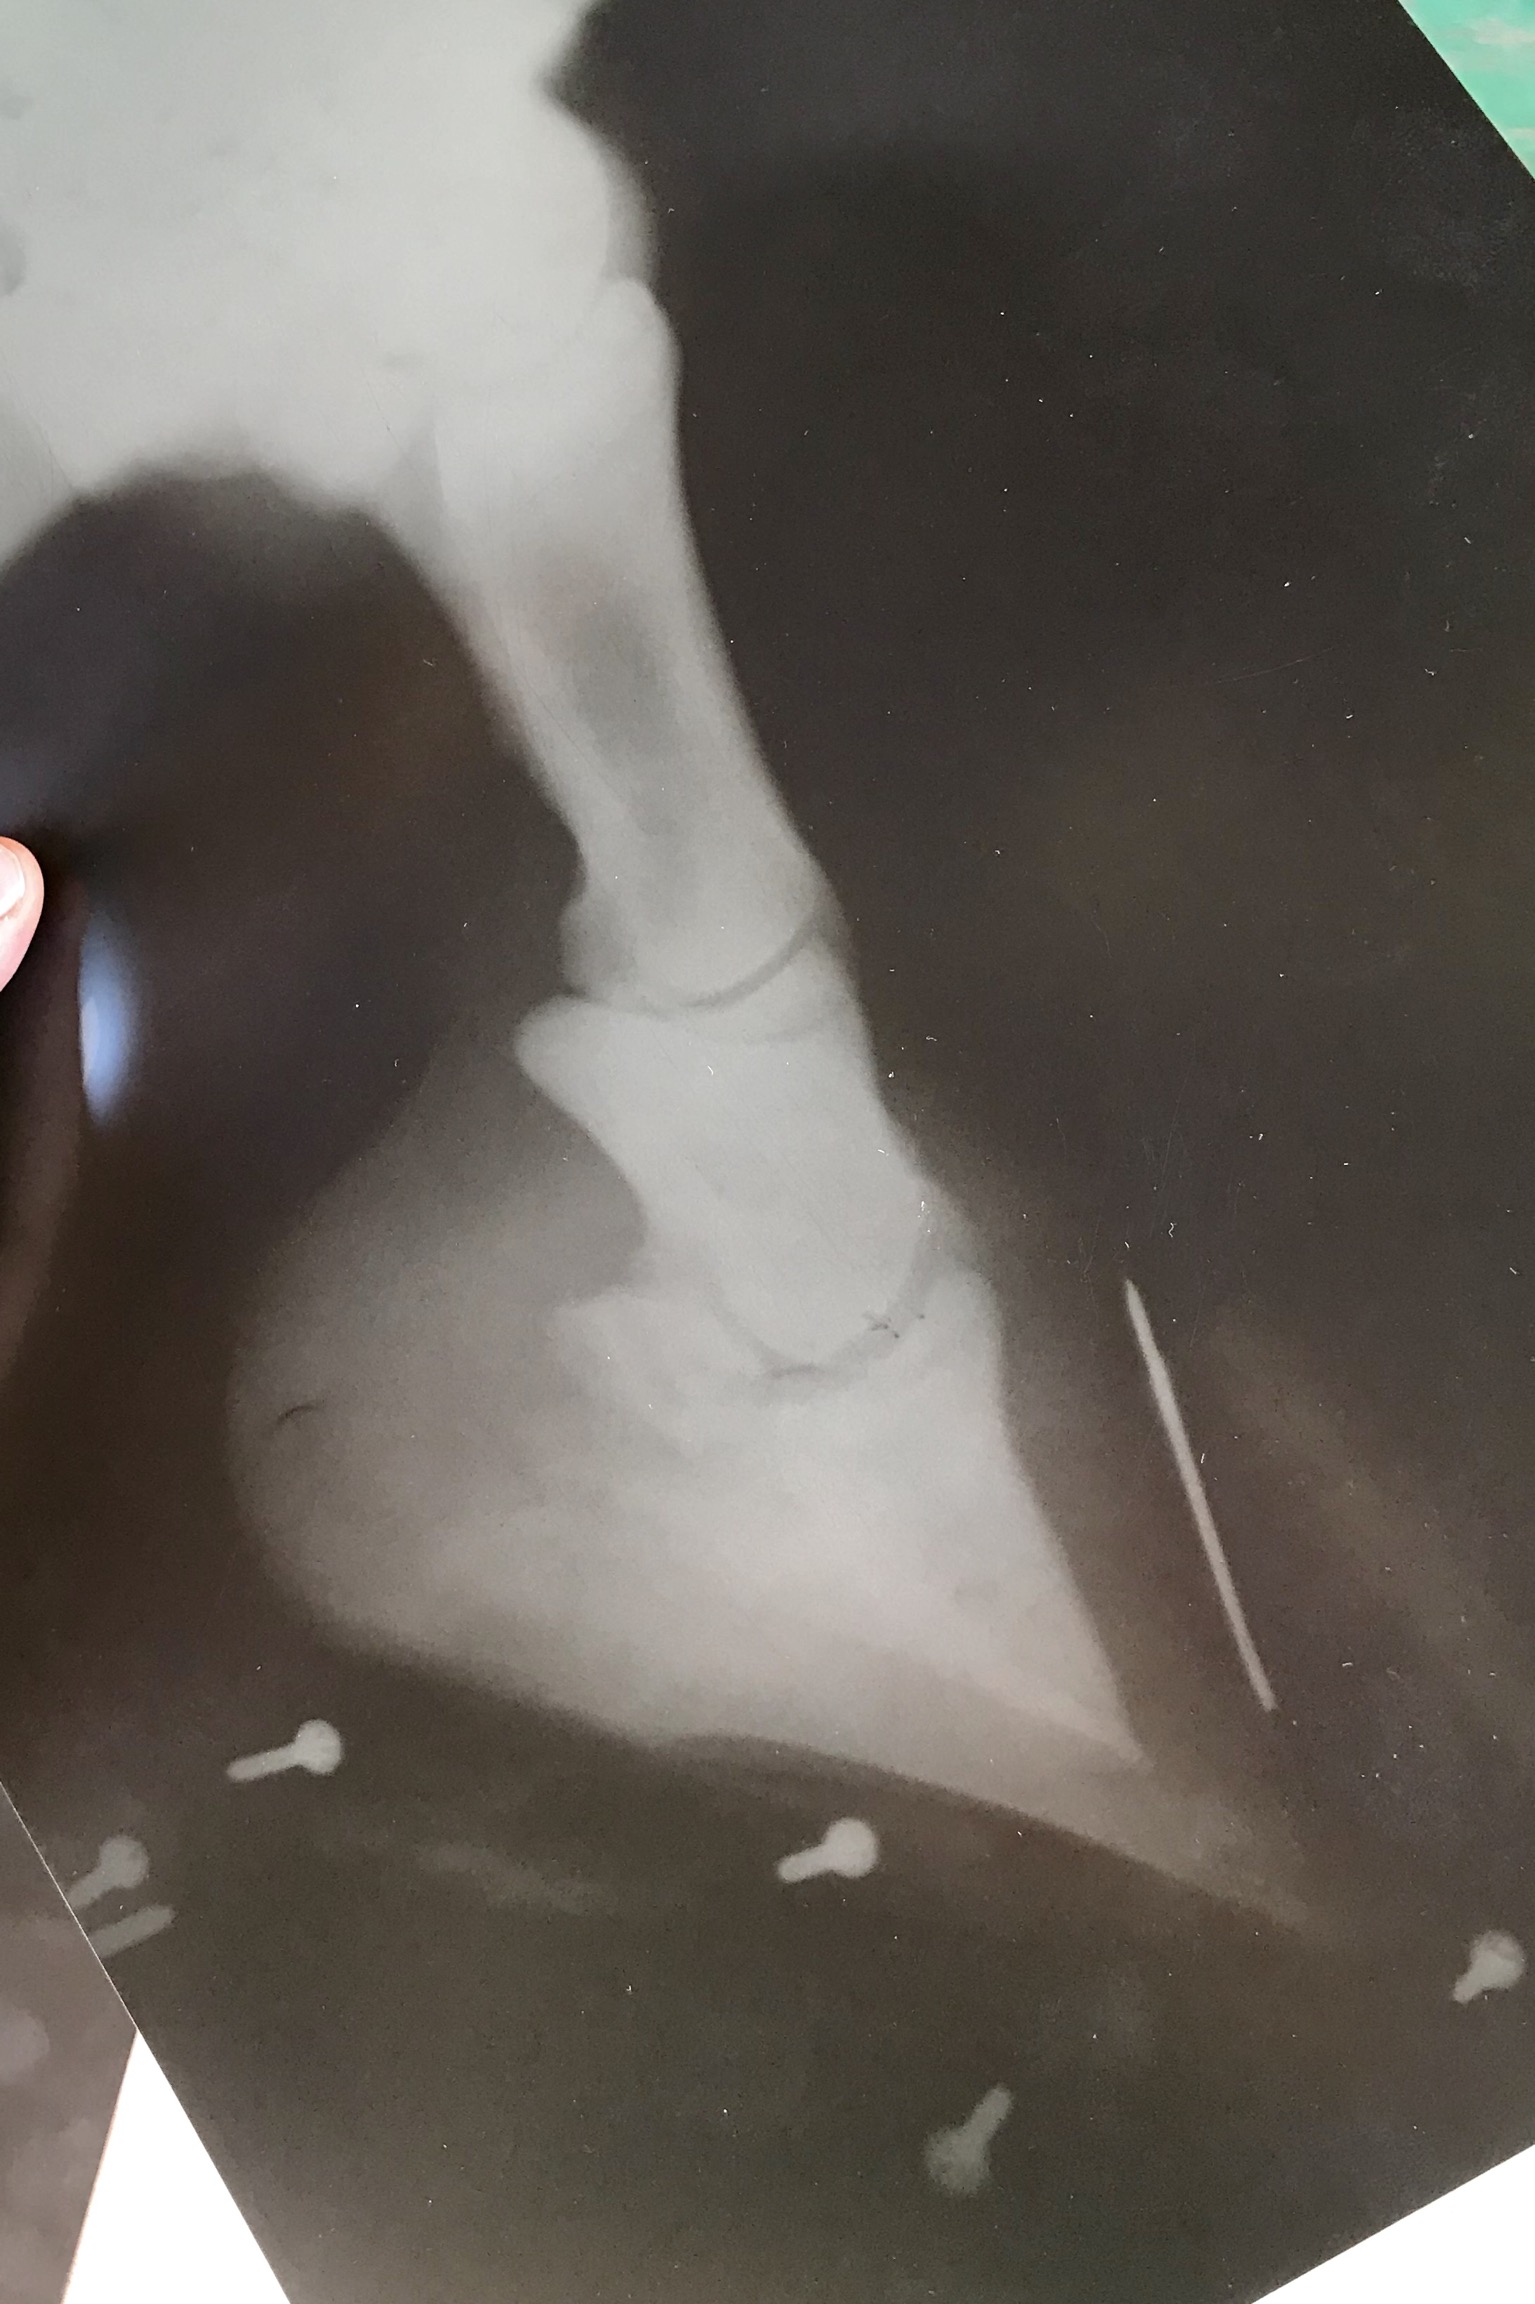

Подскажите пожалуйста, ситуация такова. Купили лошадь из деревни, продавец предупредил что конь каким-то образом обломал некоторую часть копыта переднего, не критично совсем, при этом он не хромал, ничего ему не мешало и не доставляло дискомфорт. В деревне он весь день гулял и жувал траву на мягком, травянистом грунте. Через несколько дней перевезли его к себе в клуб, и видать при перевозке, либо пока шли его грузить (дорога не благоприятная была, камни и тд) возможно намял себе копыто или ещё что-то. На данный момент шагает по мягким грунтам достаточно хорошо, но как только попадётся камешек ,как сразу видно что ему неприятно. Думала над ковкой, но рано. Ему 2,5. Вот думаю как быть, либо может просто не вытаскивать его особо, дать копыту отрасти+подавать подкормки для роста копытного рога. Ещё есть вариант поносить башмаки, пока не отрастет. Но башмаков у нас нет, поэтому если других вариантов не придумаем, будем покупать.